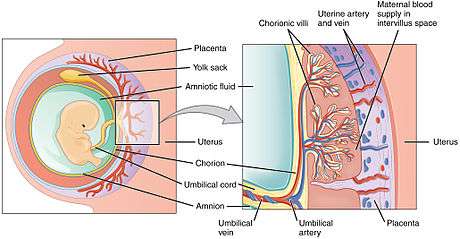

The placenta functions as a fetomaternal organ with two components: the fetal placenta (Chorion frondosum), which develops from the same blastocyst that forms the fetus, and the maternal placenta (Decidua basalis), which develops from the maternal uterine tissue.[4]

In humans, the placenta averages 22 cm (9 inch) in length and 2–2.5 cm (0.8–1 inch) in thickness, with the center being the thickest, and the edges being the thinnest. It typically weighs approximately 500 grams (just over 1 lb). It has a dark reddish-blue or crimson color. It connects to the fetus by an umbilical cord of approximately 55–60 cm (22–24 inch) in length, which contains two umbilical arteries and one umbilical vein.[5] The umbilical cord inserts into the chorionic plate (has an eccentric attachment). Vessels branch out over the surface of the placenta and further divide to form a network covered by a thin layer of cells. This results in the formation of villous tree structures. On the maternal side, these villous tree structures are grouped into lobules called cotyledons. In humans, the placenta usually has a disc shape, but size varies vastly between different mammalian species.[6]

Placental circulation

Maternal placental circulation

In preparation for implantation of the blastocyst, the uterine endometrium undergoes "decidualisation". Spiral arteries in decidua are remodeled so that they become less convoluted and their diameter is increased. The increased diameter and straighter flow path both act to increase maternal blood flow to the placenta. The relatively high pressure as the maternal blood fills intervillous space through these spiral arteries bathes the fetal villi in blood, allowing an exchange of gases to take place. In humans and other hemochorial placentals, the maternal blood comes into direct contact with the fetal chorion, though no fluid is exchanged. As the pressure decreases between pulses, the deoxygenated blood flows back through the endometrial veins.

Maternal blood flow is approximately 600–700 ml/min at term.

Fetoplacental circulation

Deoxygenated fetal blood passes through umbilical arteries to the placenta. At the junction of umbilical cord and placenta, the umbilical arteries branch radially to form chorionic arteries. Chorionic arteries, in turn, branch into cotyledon arteries. In the villi, these vessels eventually branch to form an extensive arterio-capillary-venous system, bringing the fetal blood extremely close to the maternal blood; but no intermingling of fetal and maternal blood occurs ("placental barrier").[9]